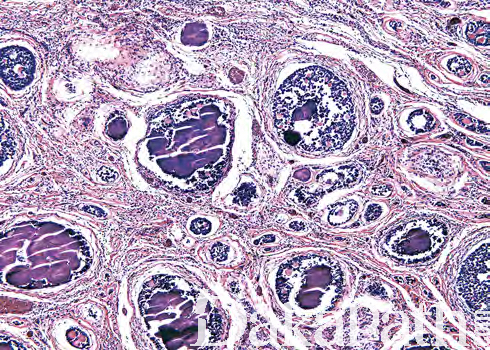

镜下见肿瘤由多个分散的圆形细胞巢构成,巢内有生殖细胞、小的间质细胞及常伴钙化的圆形基底膜样物沉积,钙化可呈砂砾体样,也可融合成大的桑椹样聚集灶;

最少部分生殖细胞为肿瘤性增生,类似于管内生殖细胞肿瘤,细胞多角形,胞浆透亮,核成角,具 1 个或多个核仁;其它生殖细胞呈精母细胞样,浆少、染色质细颗粒状或丝状,核仁不清楚;不同病例这两种细胞比例变化较大;

性索细胞胞质少,核成角,可呈栅栏状排列于细胞巢的边缘,花环样围绕基底膜样物周围(Call-Exner 小体),或围绕单一生殖细胞排列(卵泡样结构);

偶尔细胞退行性变,仅剩下特征性的钙化物,称为退行性性腺母细胞瘤;